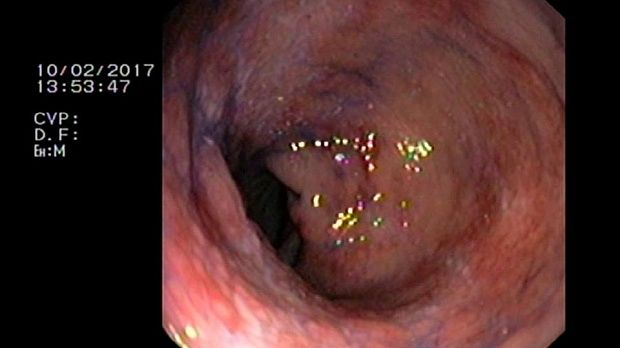

- Атлас